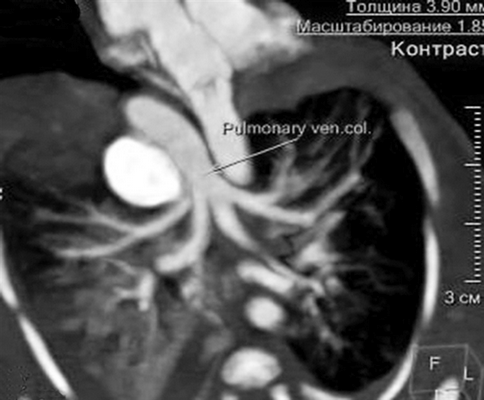

К правому легкому определено наличие двух ветвей БАЛК, одна из которых самостоятельно отходит от дуги Ао, вторая является ветвью БАЛКи, идущей также от дуги Ао, но имеющей деление на правую и левую ветви к одноименным легким соответственно. При анализе анатомии левого предсердия (ЛП) типичного расположения легочных вен (ЛВ) не отмечалось. Полость, сообщающаяся с ЛЖ, вбирала в себя единый венозный коллектор ЛВ, в который дренировались ЛВ обоих легких. Таким образом, был сделан вывод о том, что полость сообщающаяся с ЛЖ и включающая в себя единый венозный коллектор ЛВ, является ЛП (рис. 9). Анализируя структуры МПП и МЖП, отмечались множественные дефекты перегородок.

Рис. 9. МСКТ, аксиальная проекция, показан единый коллектор легочных вен

По результатам проведенного исследования было сделано заключение о наличии у пациента врожденного порока сердца — атрезия ЛА IV типа, БАЛКи ДМПП, ДМЖП, единый коллектор ЛВ в условиях эктопии сердца.